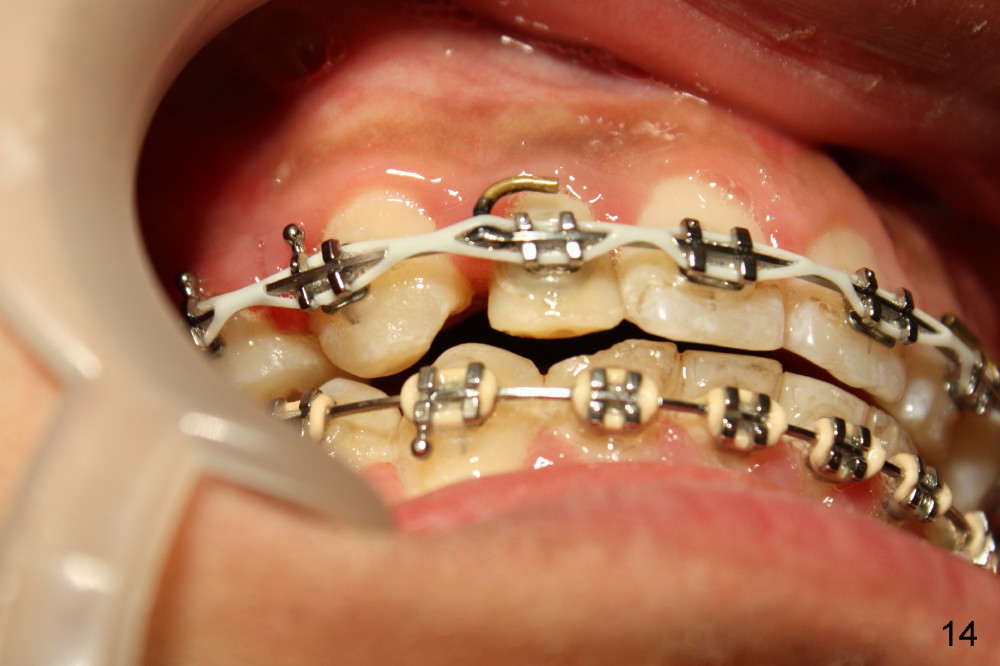

Fig.13-15 shows the upper incisors totally 4.5 month of retraction. The upper left canine (Fig.15: #11) seems to be distalized too much, as compared to the dashed line. Therefore whole arch power chain is placed with an intention to bring the canine mesially (arrowhead) while continue distalizing the incisors (including #10 (arrowhead).